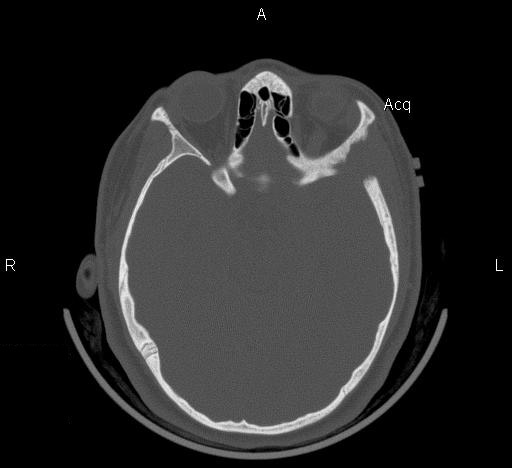

Clinical information: The patient was a 13 year-old girl who presented with worsening headache and some difficulties with memory, concentration and attention. MRI studies disclosed a 2.1 x 1.9 x 1.8 cm enhancing mass in the left temporal bone and sphenoid wing. The mass extended intracranially and abuts the left temporal bone accompanied by dural enhancement at that location. There is also extension through the bone into the submuscular temporal region. The following photos are taken from representative regions of the lesion. Panel 1 and 2 are CT scans at soft tissue and bone density respectively. Panel 3 and 4 are T1 weighed images without and with contrast respectively. Pandl 5 is proton density image. Panel A to D are cytologic (squash) prepartion for intra-operative consultation. Panel E and F are frozen sections for intraoperative consultation. Panel G to L are paraffin embedded sections.

| 1. | 2. | 3. | 4. | 5. |